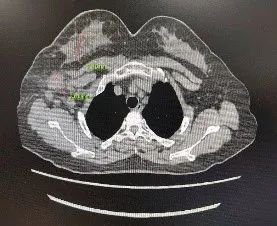

▌影像学评估(CT):

图4. 基线与6周期治疗后CT影像